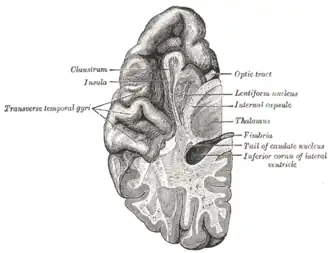

Section of brain showing upper surface of temporal lobe. | |